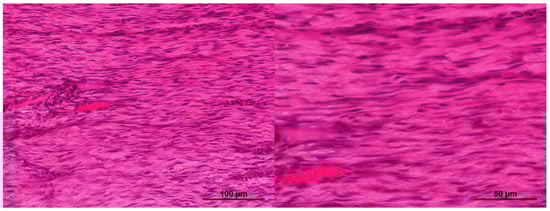

2. Results and Discussion

2.1. Characteristics of the Condition of the Wounds on Day 7 of the Study

2.2. Characteristics of the Wound Defect Condition on Day 42 of the Study

3.11. Morphological Studies of Biomaterial

3.11.1. Light Microscopy